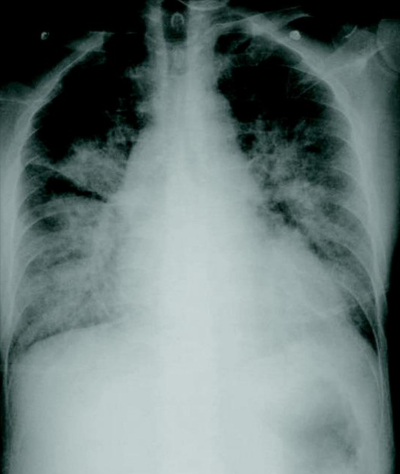

血液所見:赤血球 350 万、Hb 11.6 g/dL、Ht 39 %、白血球 9,600、血小板 21 万。血液生化学所見:AST 30 U/L、ALT 26 U/L、尿素窒 素 14 mg/dL、クレアチニン 0.6 mg/dL、血糖 99 mg/dL、Na 136 mEq/L、K3.8 mEq/L、Cl 100 mEq/L。心電図では明らかな ST-T 変化は認めない。胸部エックス線写真及び心エコー図を別に示す。